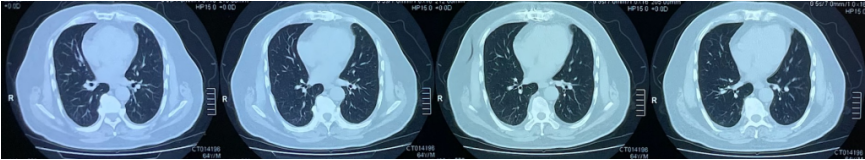

入院6天前(12月28日)气短加重,就诊于当地医院,指脉氧饱和度80%(未吸氧),新冠病毒抗原自测(+)。血常规:WBC 1.99×109/L,LYM 0.71×109/L,hsCRP>5 mg/L;胸部CT:双肺多发条索影(图1)。予甲强龙40 mg、抗细菌感染及阿兹夫定治疗3天效果欠佳,转入我院。

图片

图1  外院胸部CT(2022年12月28日)

1月3日化验检查:WBC 4.76×109/LNEU 4.07×109/LLYM 0.46×109/LCRP 112.76 mg/L;D-二聚体0.65 mg/L;Fet 747.9 ng/ml,IL-6 267.53 pg/ml,新冠核酸阳性(CT值25)。予“Paxlovid(1月4日)”“甲强龙40 mg”“托珠单抗(1月5日)”治疗。1月5日患者气短加重,查血气分析(高流量FiO2 0.8):pH 7.42,PaCO2 30.5 mmHg,PaO2 62.3 mmHg,HCO3- 25 mmol/L,Lac 1.6 mmol/L,PFR 77.87 mmHg。1月3日胸部CT示双肺多发斑片影,磨玻璃影,以胸膜下和右肺为著(图2)

图2  我院胸部CT(2023年1月3日)

胸部影像:双肺多发磨玻璃、斑片影(下肺及胸膜下为著),肺容积缩小;